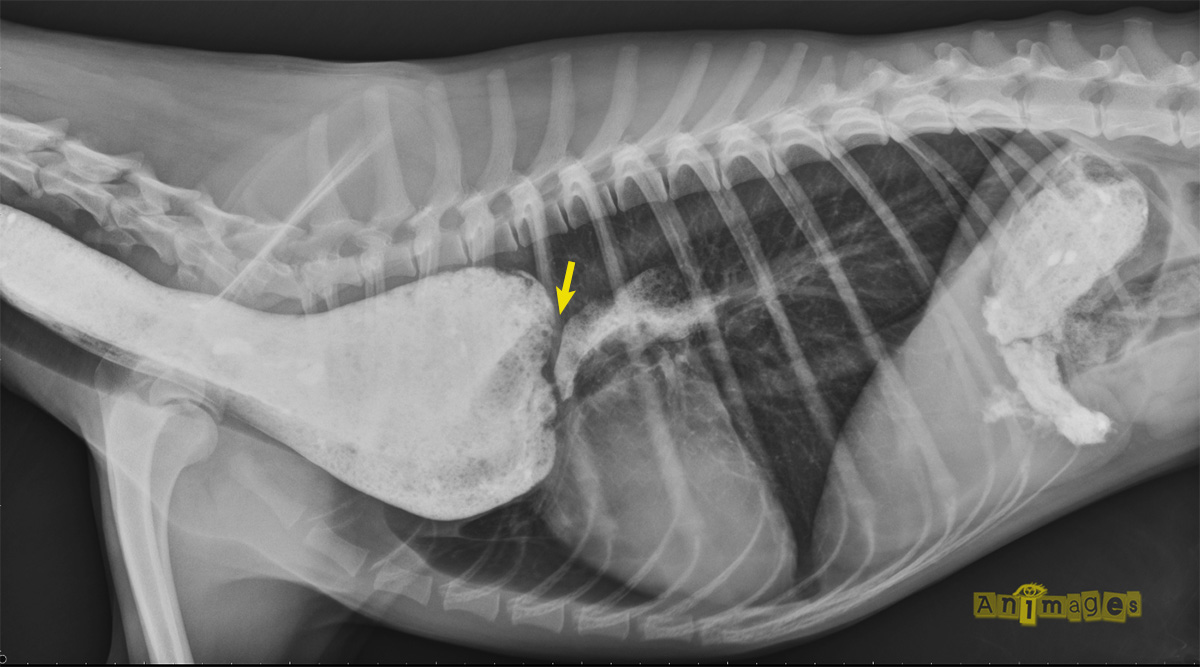

Il s’agissait – comme la majorité d’entres vous le suspectiez – d’un mégaoesophage congénital. L’oesophage (flèches jaunes) est sévèrement dilaté par de la nourriture, déplaçant et comprimant la trachée ventralement. La VD révèle également un patron alvéolaire au lobe moyen droit avec de beaux bronchogrammes aériques (voir image magnifiée), compatible avec une pneumonie par aspiration (fausse déglutition). Pourquoi ce patron n’est pas reconnu sur la latérale ? Simplement parce qu’il s’agissait d’une latérale droite qui force le poumon droit à s’affaisser au profit du poumon gauche, limitant ainsi le contraste radiographique nécessaire à la distinction de cette pathologie. On remarque aussi sur la VD la silhouette du thymus formant un signe de « voile » s’étendant vers la gauche.

Lors d’anomalies vasculaire constrictive – une persistance de la 4e arche aortique étant la principale anomalies rencontrée chez le chien (comme ci-bas, après administration de baryum liquide) -, l’oesophage n’est généralement dilaté que crânialement au site d’obstruction (flèche jaune), bien que sa portion caudale puisse aussi devenir dysfonctionnelle et dilater, mais en laissant un site de rétrécissement à la base du coeur. L’estomac semble en place dans ce cas-ci, excluant une intussusception gastro-oesophagienne. Une obstruction oesophagienne caudale (corps étranger ou stricture) représentait un diagnostic différentiel plausible.